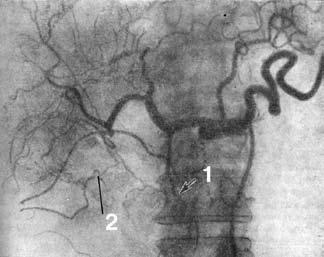

Диагноз основывается на изменениях, обнаруживаемых на панкреатограммах (стеноз или обструкция протока ПЖ), характер которых зависит от размеров опухоли, ее локализации и взаимоотношения с протоковой системой органа. Опухоль, исходящая из эпителия ГПП или располагающаяся в непосредственной близости от него, даже при небольших размерах быстро приводит к изменениям во всей системе протоков. При локализации рака на некотором расстоянии от ГПП изменения в первую очередь возникают в мелких протоках, тогда как в главном протоке их нет (рис. 108). Ангиография (АГ). При РПЖ возникают изменения в ее сосудах или сосудах, расположенных в непосредственной близости к железе: изменяется просвет и положение сосудов, нарушается кровоток, появляются атипичные сосуды. Существует несколько методик контрастирования артерий и вен ПЖ: 1) спленопортография, 2) чрескожная чреспеченочная портогепатография, 3) целиакография. Для опухоли характерны смещение, деформация, окклюзия сосудов. Диагностическая точность метода составляет около 70 % (рис. 109).

Рис. 109. Целиакограмма: рак головки поджелудочной железы. Артериальная фаза. Ампутация желудочно‑двенадцатиперстной артерии (1), обеднение сосудистого рисунка в зоне опухоли (2).